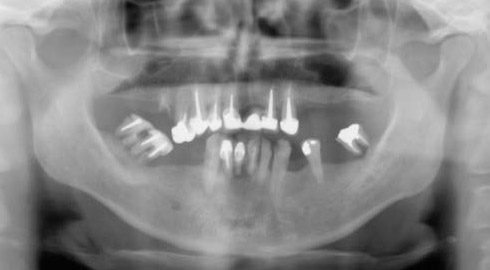

Exemple d’une réhabilitation complète implantaire

Situation clinique initiale